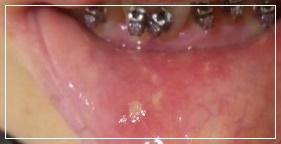

피곤하면 우리는 흔히 ‘입병이 생겼다, 입안이 헐었다’라는 말을 쓰곤 합니다. 입병이란 정확히는 구내염이라 하여 잇몸, 혀, 볼 점막, 입술 안쪽 등 구강 내 모든 연조직에 생길 수 있는 염증성 병변을 말합니다. 대개는 하얗게 움푹 파이는 모양으로 나타난다.입술 혹은 입안, 혓바닥 구내염은 은근한 통증을 안깁니다. 오늘은 흔하게 생기는 질환중에 하나인 구내염에 대해서 알아보겠습니다.

구내염의 증상으로는 음식을 먹을 때 입 안의 통증이나 따가움, 열이 나는 느낌이 있으며, 구취가 생기기도 합니다. 종류에 따라 피부병과 같은 증상이 나타나기도 하고 통증의 악화와 완화가 반복적으로 지속됩니다. 심한 경우에는 음식을 씹기가 힘들어지고 빨간 반점과 깊은 궤양이 생기며 궤양이 되면 심한 통증, 연하 장애, 언어 장애 등이 나타날 수 있습니다.